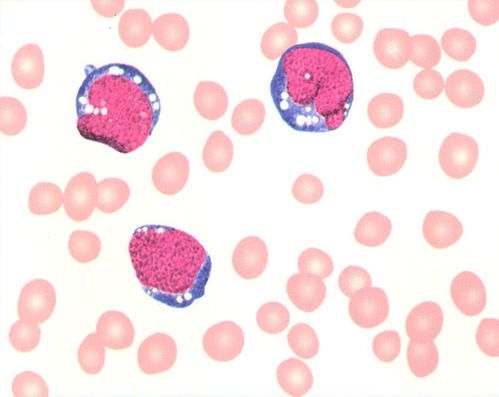

(1)血象白细胞计数多增高,可见幼稚淋巴细胞及异型淋巴细胞。血小板正常或减少。

(2)骨髓象增生活跃至极度活跃,幼稚和原始淋巴细胞占25%以上。